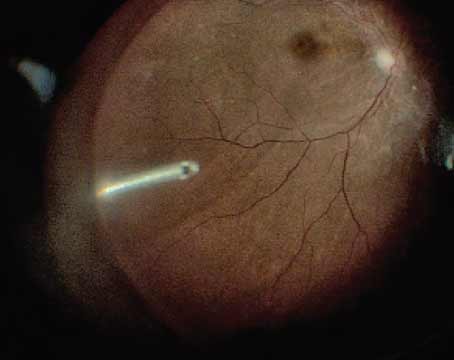

Surgical Pearl Video

Pearls for fovea-sparing ILM peeling

A potentially effective strategy for avoiding postoperative macular hole formation in myopic traction maculopathy.